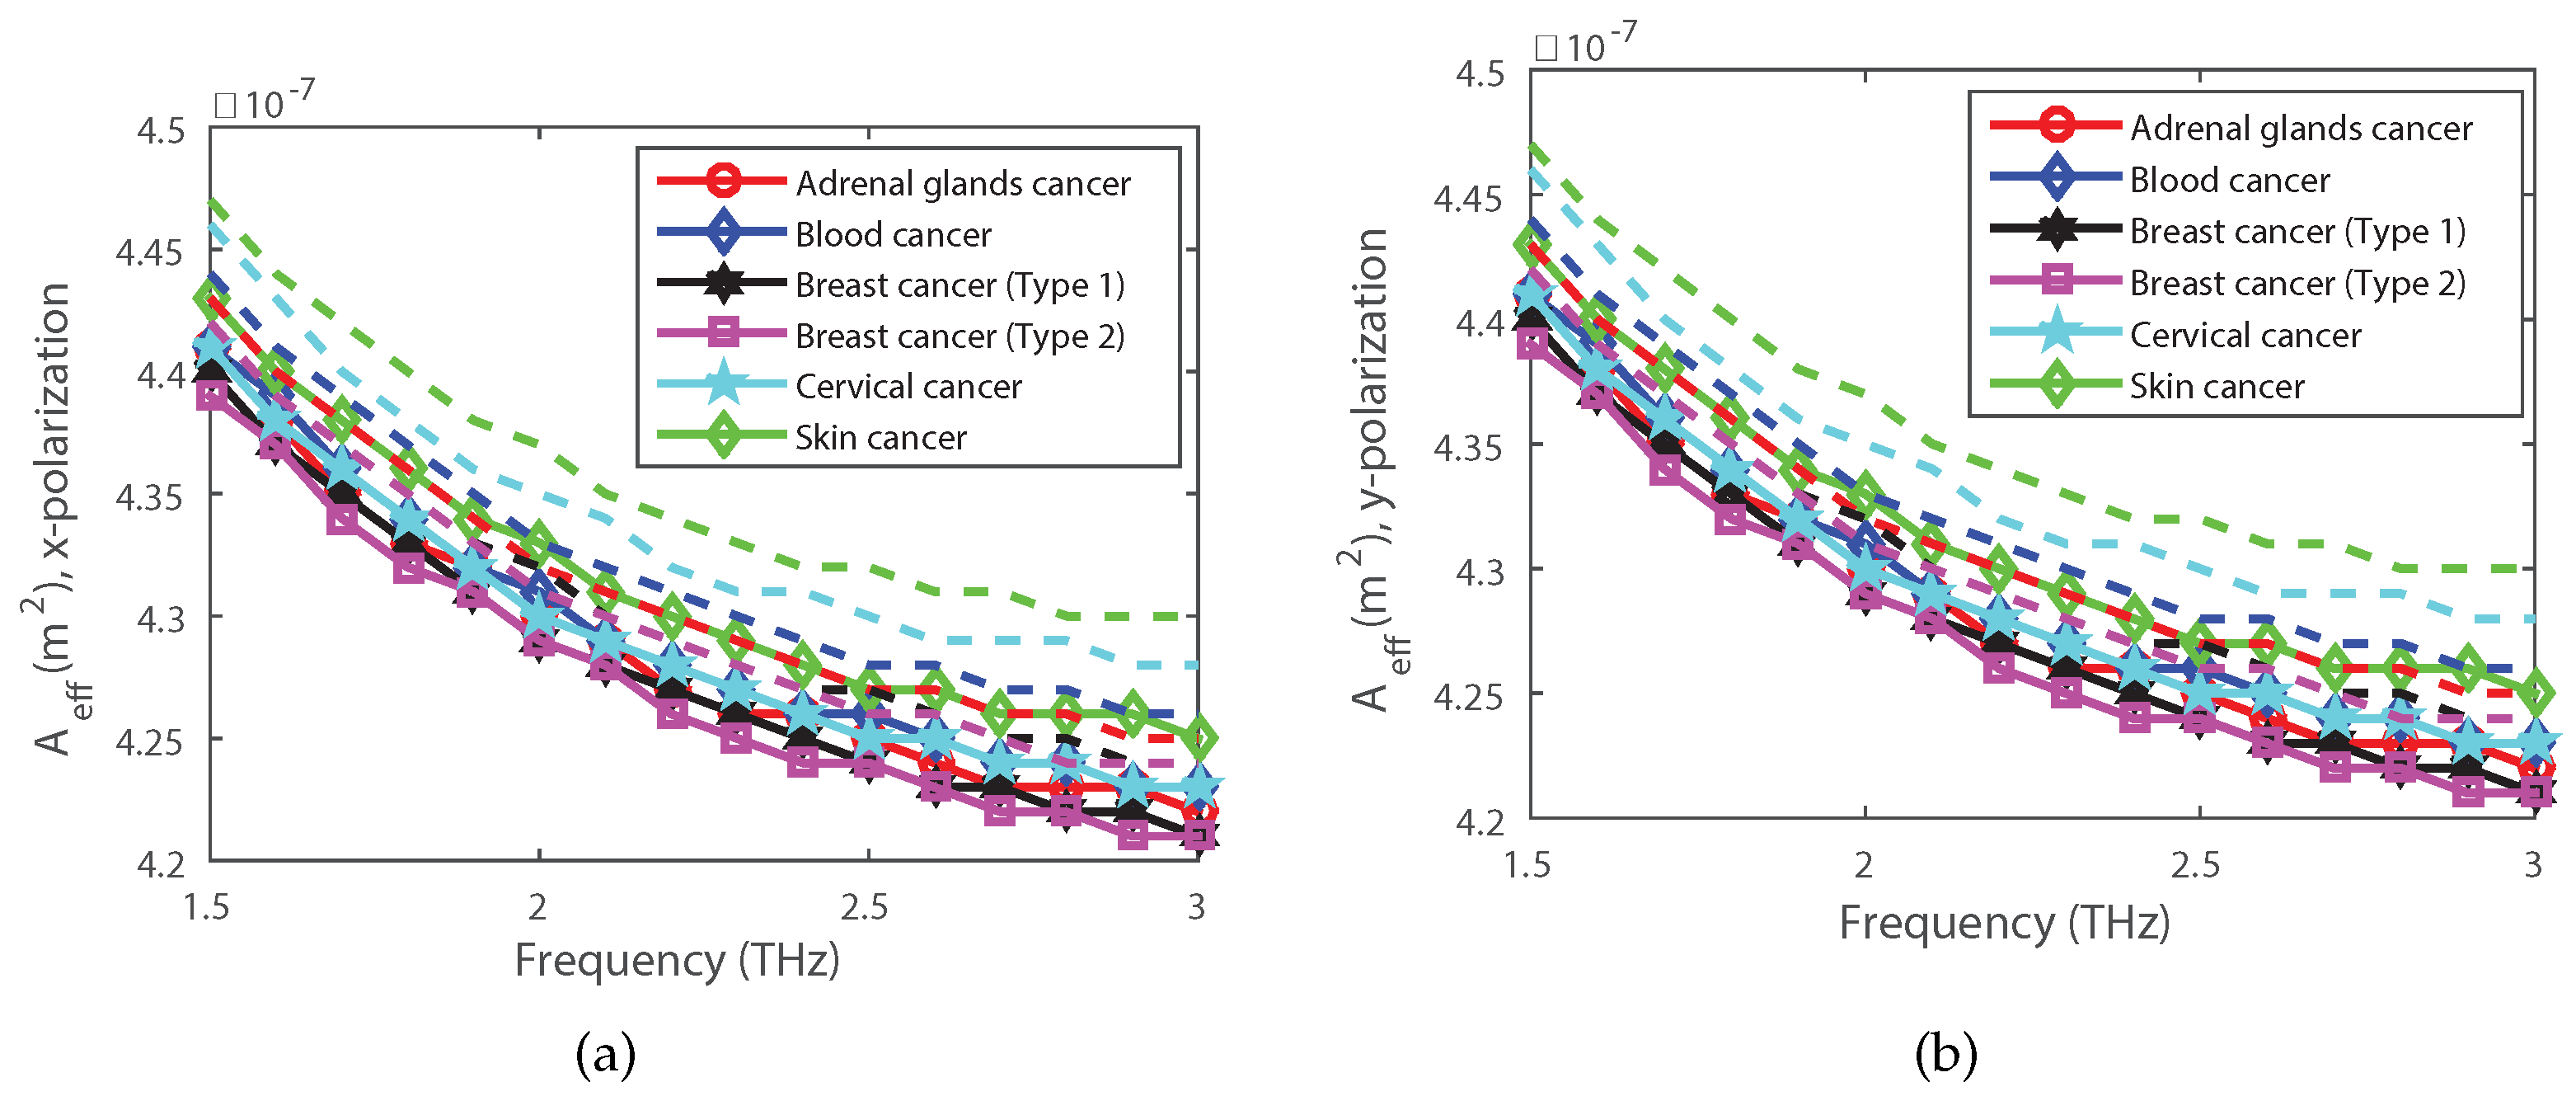

4. Simulation Results and Discussions